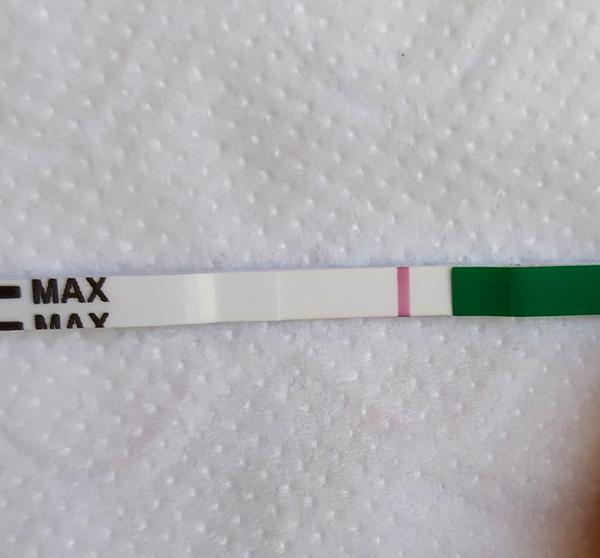

Duch na teste

ahojte babule, mam taku otazku...mate skusenost ze pocas 3 dni vam nesilnela druha ciarka na teste ale bola rovnaka???ako duch????

@popuska aj ja vidim 🙂 drzim prsty nech silnie kazdym dnom ❤

@123vika krasne silneju ❤

Vsetkym Vam drzim prsty nech Vam tie ciarocky silneju 👍😍